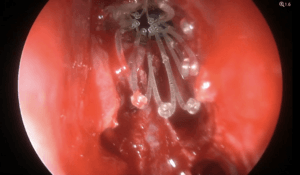

Resección de schwannoma vestibular Koos III guiada con fluoresceína

El prof. Mastronardi realiza la resección microquirúrgica de un schwannoma vestibular Koos III guiada con fluoresceína mediante abordaje retrosigmoideo.